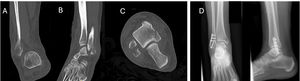

In SAD-2, where there is an associated vertical fracture of the medial malleolus, a CT scan is recommended to rule out joint impaction of the internal column, which can occur in 61–73% of cases.18,24 In this type of fracture, surgical treatment of both malleoli is required. For fixation of the medial column, it is recommended to follow the same principles as for treatment of a tibial pilon, using a medial plate to improve biomechanical support, and to restore joint collapse18,25 (Fig. 3).

(A–D) Example of transverse fracture of the infrasyndesmotic fibula SAD-2 with vertical line in the internal column. (E and F) CT image showing medial impaction and articular cartilage collapse. (G and H) Postoperative X-rays showing osteosynthesis using anatomical fibula plate, anti-glide plate in internal column, K-wire, and lag screw to restore the articular surface.